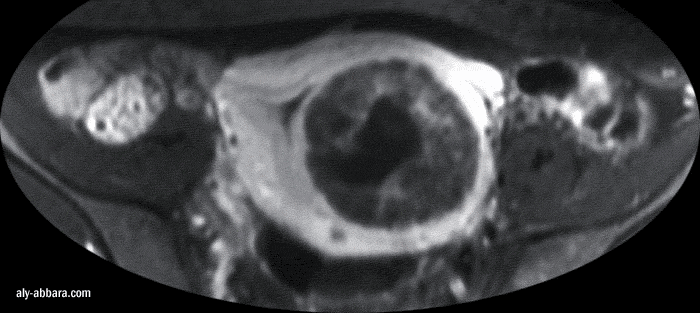

IRM (Imagerie par Résonance

Magnétique) - coupe coronale de l'utérus

Fibrome utérin (myome) sous muqueux endocavitaire avec nécrobiose

aseptique

à l'origine de multiple foyers kystiques au sein du fibrome

Ce fibrome est

à l'origine de ménorragie et d'anémie